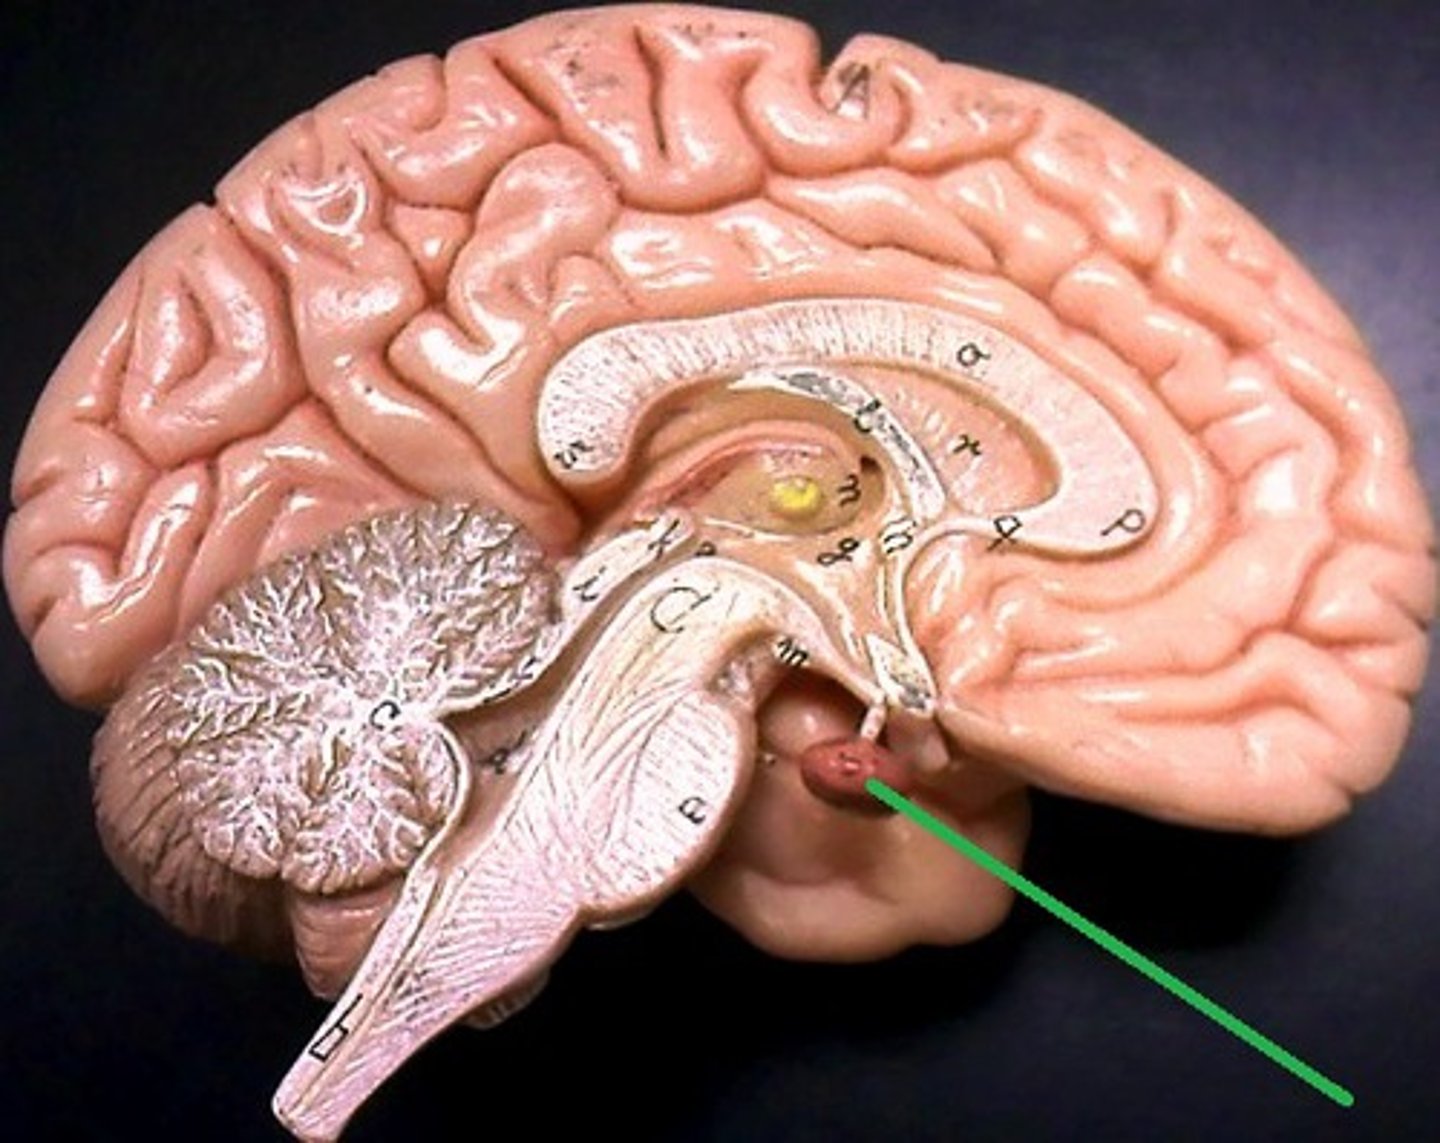

hypothalumus

small area near the base of the brain that is above the pituitary gland

pituitary gland

gland at the base of the brain that dangles under the hypothalamus

Pineal Gland

small pea sized gland that can be found posterior to the thalamus

hypothalamus hormones

ADH, oxytocin, regulatory hormones

pituitary gland hormones

LH, FSH, GH, TSH, ACTH, Prolactin, Oxytocin, ADH

pineal gland hormone

melatonin